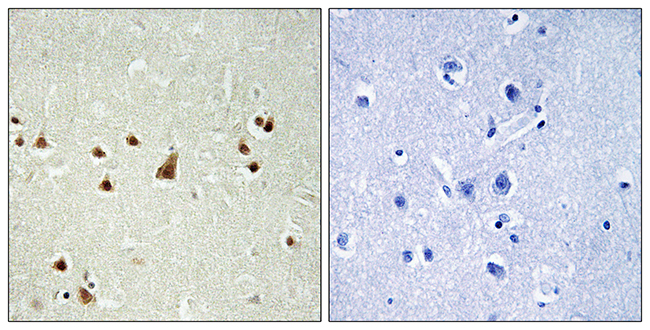

Anti-TBX1 AntibodyA99987

ApplicationsImmunoFluorescence, Western Blot, ELISA

ReactivityHuman

Anti-ST14 AntibodyA99988

ApplicationsImmunoFluorescence, Western Blot, ELISA

ReactivityHuman

Anti-SMG7 AntibodyA99989

ApplicationsImmunoFluorescence, Western Blot, ELISA

ReactivityHuman